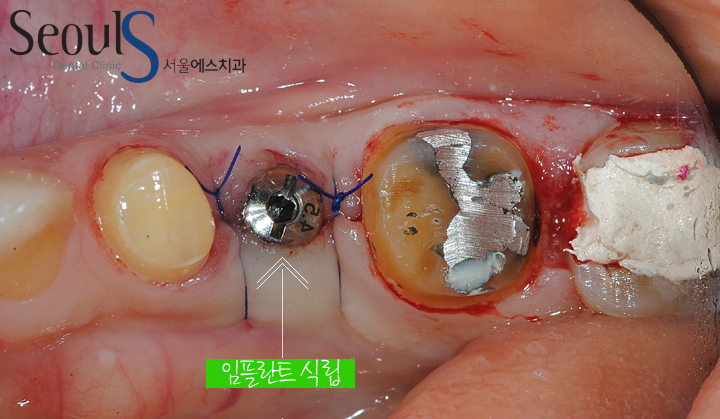

임플란트를 식립했습니다

임플란트 식립 후 X-ray 모습입니다

정확한 위치에 임플란트가 식립 되었고 잇몸뼈와 단단히 굳으면

임시치아 과정을 거쳐 최종치아를 결합합니다